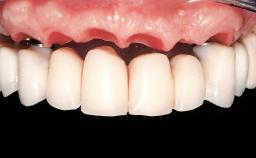

Immediate Loading of Eight Implants in the Maxilla and Six Implants in the Mandible and Final Restoration with Three-Unit and Four-Unit FDPs

German Gallucci, Jean-Pierre H Bernard, Urs C Belser

# of Implants 14